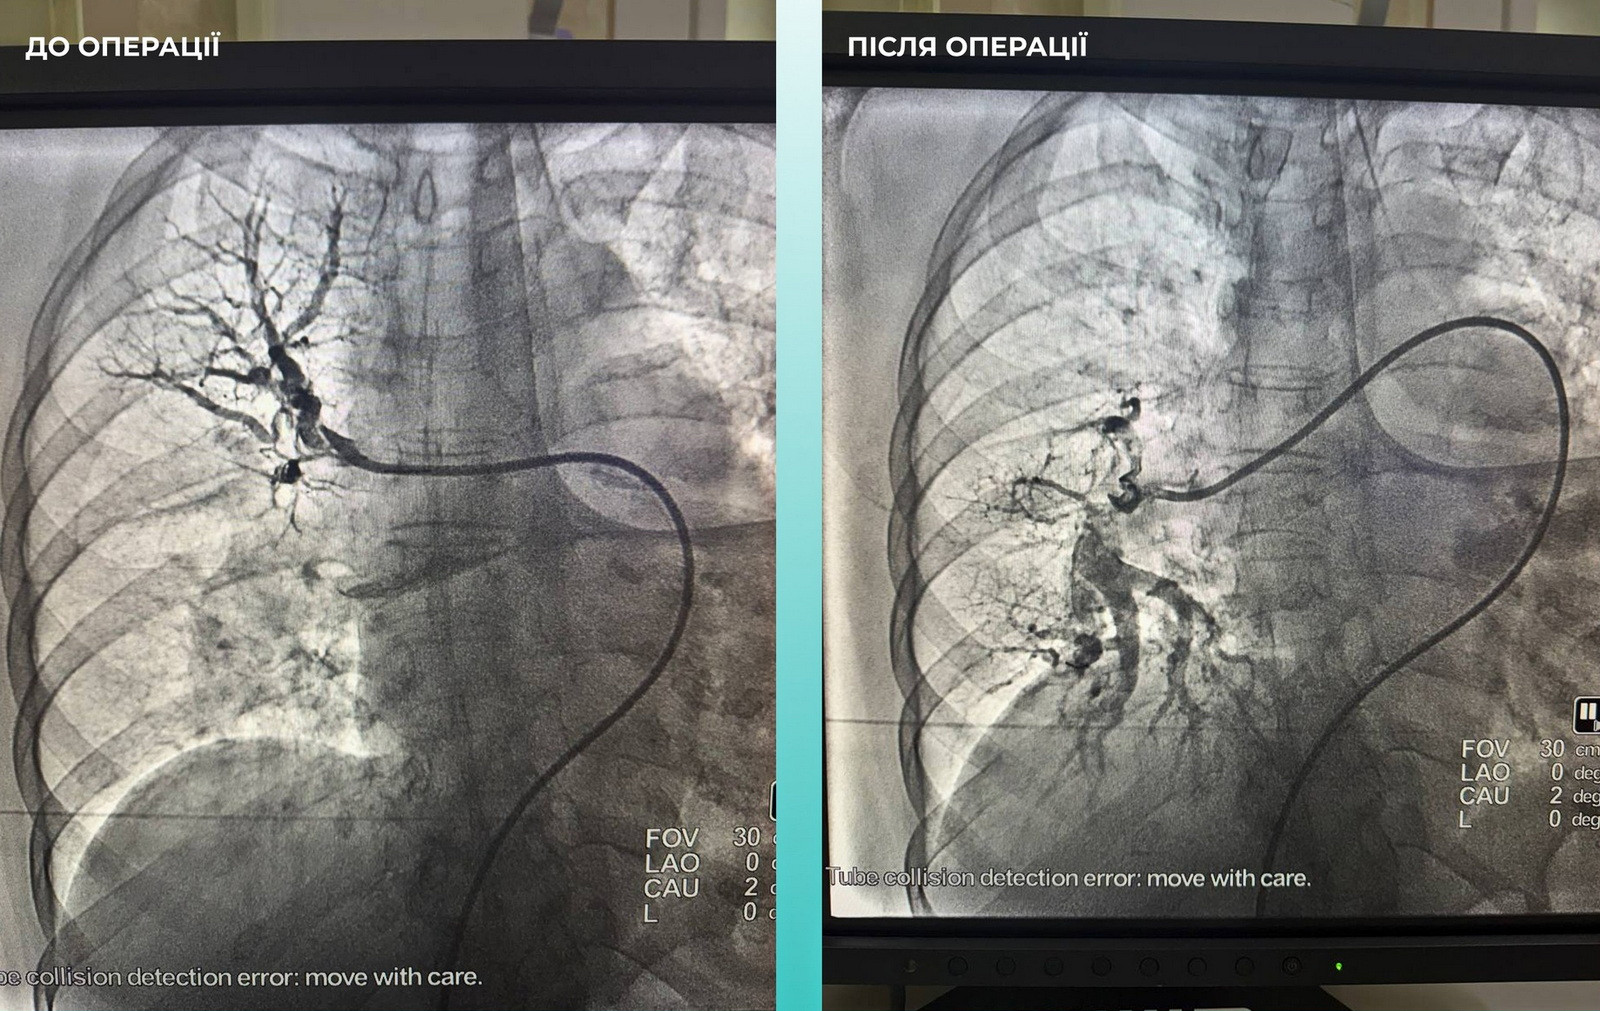

Одеситка потрапила до медзакладу з важким гострим мозковим інсультом, а під час обстеження на комп’ютерному томографі лікарі виявили закриття середньої мозкової артерії. Медики також зафіксували, що пацієнтці важко дихати, тому додатково обстежили легені і встановили тромбоемболію легеневої артерії.

Мультидисциплінарна команда лікарів ухвалила рішення провести одночасну тромбоектомію з мозкової та легеневої артерій. Операція пройшла успішно, наразі пацієнтка почувається значно краще, вона перебуває при свідомості та вже рухає кінцівками.